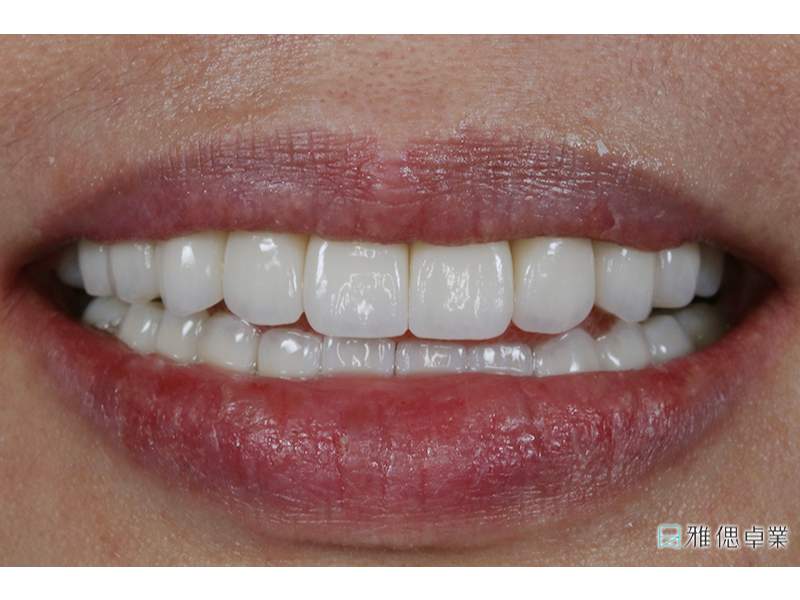

術後